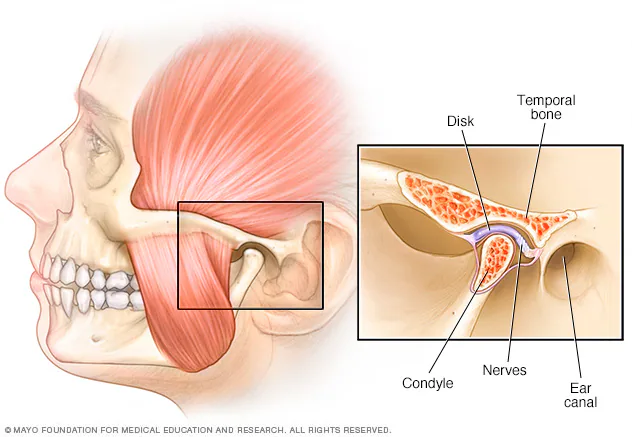

Az állkapocsízület

Az állkapocsízület az állkapocs és a koponya közötti ízület. A hallójárat előtt helyezkedik el. Testünk egyik legösszetettebb, legérzékenyebb ízülete. Egyszerre végez forgó és csúszó mozgást. Egyaránt fontos szerepet játszik a rágásban, beszédben és légzésben.

A fogazat, a rágóizmok, a szalagok és az ízület kényes egyensúlyban vannak. Ehhez indirekt módon hozzátartozik még a csontozat többi része is – a testtartás is okozhat gnatológiai problémákat.